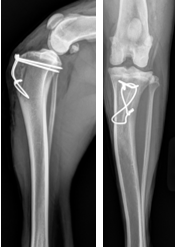

Medial Patellar Luxation (MPL)